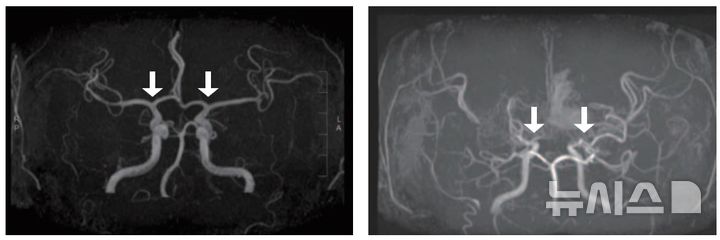

[서울=뉴시스] 사진 왼쪽부터 정상 및 모야모야병 환자의 뇌혈관. (사진= 서울대병원 제공)

모야모야병은 뇌로 혈액을 공급하는 혈관이 원인 없이 점차 좁아지는 만성 진행성 뇌혈관질환이다. 10세 전후 소아와 40세 전후 성인에서 주로 발병하며, 부작용으로는 뇌혈관이 막히거나 파열되는 허혈성·출혈성 뇌졸중이 있다.